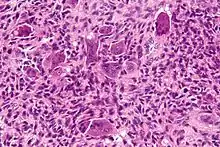

High magnification micrograph of an aneurysmal bone cyst

High magnification micrograph of an aneurysmal bone cyst Intermediate magnification micrograph of an aneurysmal bone cyst